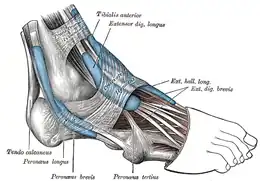

Les muscles extrinsèques du pied sont situés dans la jambe et seuls leurs tendons sont présents dans le pied. On distingue quatre groupes selon la position de ces tendons au passage de la cheville : postérieur, médial, antérieur et latéral.

Le groupe latéral passe en arrière de la malléole latérale et dans le rétinaculum fibulaire, et se continue sur le bord latéral du pied. Il contient les tendons des muscles long fibulaire et court fibulaire, qui permettent l'éversion du pied.

Le groupe antérieur passe dans le rétinaculum des extenseurs et se continue sur le dos du pied. Il contient les tendons des muscles tibial antérieur, qui permet la flexion dorsale de la cheville et l'inversion du pied, long extenseur de l'hallux et long extenseur des orteils, qui permettent l'extension des orteils et la flexion dorsale de la cheville, et troisième fibulaire, qui permet la flexion dorsale de la cheville et l'éversion du pied.